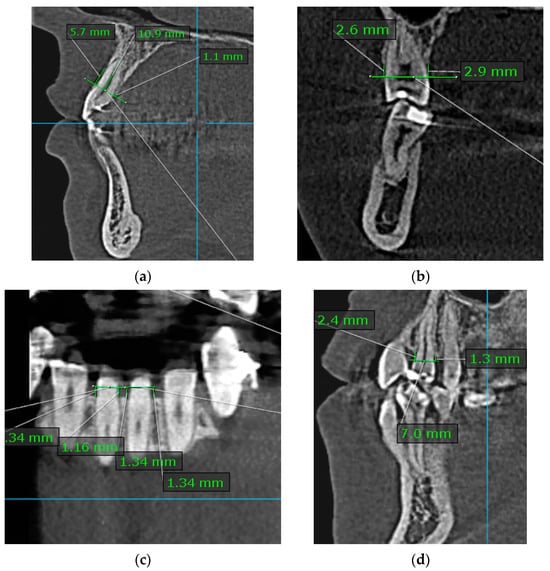

2.1.2. Assessment of Alveolar Bone Level (ABL)

- Buccal and lingual ABL (B/L-ABL) measurements were performed in the sagittal plane for anterior teeth and in the coronal plane for posterior teeth.

- Mesial and distal ABL (M/D-ABL) measurements were performed in the coronal plane for anterior teeth and in the sagittal plane for posterior teeth.

2.1.3. Assessment of Root Length (RL)

- Measurements were taken in the sagittal plane at the CIs of maxillary and mandibular teeth (Figure 2).